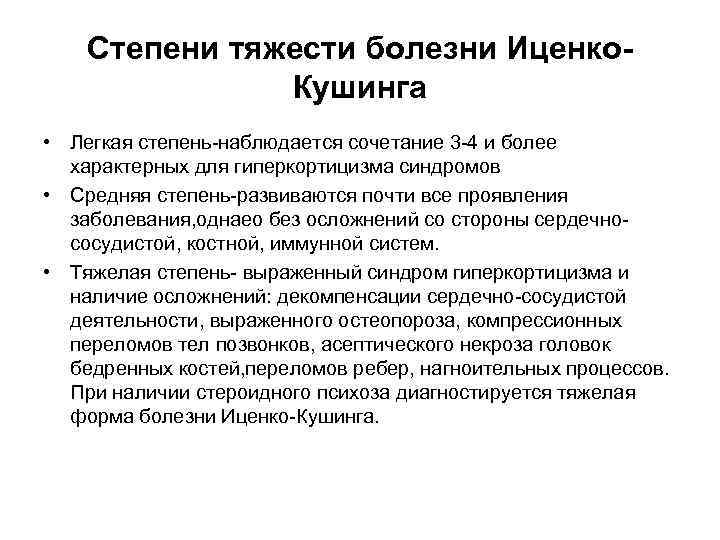

Степени тяжести болезни Иценко. Кушинга • Легкая степень наблюдается сочетание 3 4 и более характерных для гиперкортицизма синдромов • Средняя степень развиваются почти все проявления заболевания, однаео без осложнений со стороны сердечно сосудистой, костной, иммунной систем. • Тяжелая степень выраженный синдром гиперкортицизма и наличие осложнений: декомпенсации сердечно сосудистой деятельности, выраженного остеопороза, компрессионных переломов тел позвонков, асептического некроза головок бедренных костей, переломов ребер, нагноительных процессов. При наличии стероидного психоза диагностируется тяжелая форма болезни Иценко Кушинга.

Степени тяжести болезни Иценко. Кушинга • Легкая степень наблюдается сочетание 3 4 и более характерных для гиперкортицизма синдромов • Средняя степень развиваются почти все проявления заболевания, однаео без осложнений со стороны сердечно сосудистой, костной, иммунной систем. • Тяжелая степень выраженный синдром гиперкортицизма и наличие осложнений: декомпенсации сердечно сосудистой деятельности, выраженного остеопороза, компрессионных переломов тел позвонков, асептического некроза головок бедренных костей, переломов ребер, нагноительных процессов. При наличии стероидного психоза диагностируется тяжелая форма болезни Иценко Кушинга.